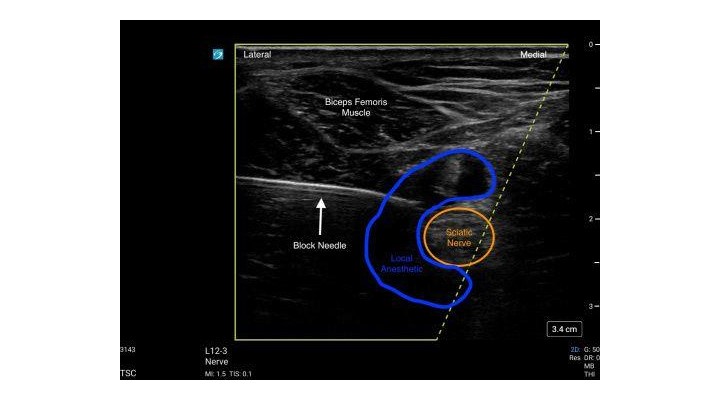

- The block needle is inserted using the in-plane approach from lateral to medial.

- Local anesthetic is deposited around the Sciatic Nerve.

- The block needle may be repositioned under ultrasound guidance to ensure adequate spread of local anesthetic around the Sciatic Nerve.